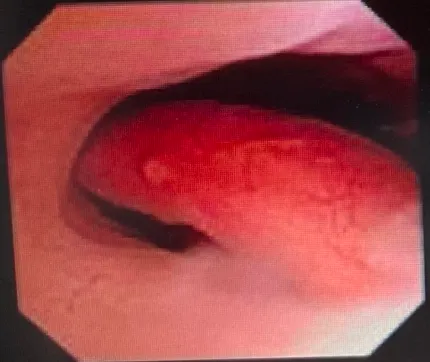

5/2跟王懷麟討論完後,決定就切入到植入模式,每個月監測卵泡情況,基礎卵泡數有變多的話(>5顆),那就切換到取卵模式。植入要有些準備,包括我子宮瘜肉切除,ERA要再做。這樣就要耗掉兩個月,也就是說,可以再看兩個月的卵泡,如果沒有的話,就是手頭上胚胎一直植入。

子宮瘜肉我問了王懷麟,宜蘊其實有做,但現在卡住的是冷刀耗材。現在冷刀耗材大缺貨,宜蘊只剩下3隻在台中,如果我要做的話,就是要殺去台中做手術。我跟王懷麟說,我先去台大找楊政憲,看台大那邊有沒有冷刀,沒有的話我再回來找你。

手術要全麻,我問楊政憲,需不需要提前去塞海藻棒。海藻棒是軟化子宮頸用的,冷刀有分尺寸,比較大的才需要塞海藻棒、比較小的不需要。

他看我有點猶豫想要排尺寸大的刀,他說,現在大尺寸的就是缺貨,只有冷刀的選項。

我問楊政憲怎麼確認術後情況,他說就是下個月生理期後再檢查一次。

其實王懷麟也會用子宮鏡幫我檢查,但楊政憲複驗、王懷麟再複驗,我覺得那應該可以了。